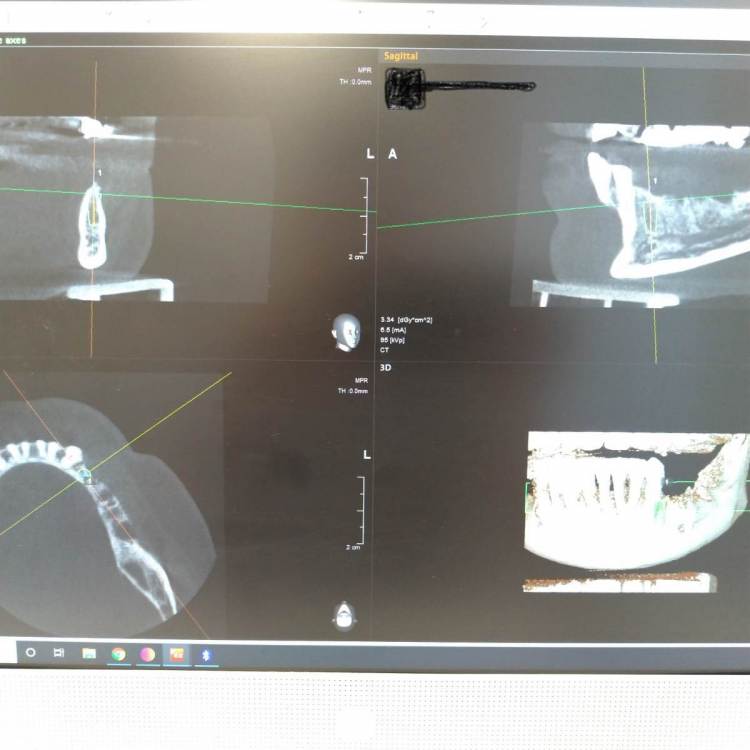

HAV Опубликовано 4 апреля, 2022 Поделиться Опубликовано 4 апреля, 2022 Всем доброго времени суток. Сомневаюсь - как поступить в данной ситуации, делать НКР, или обойтись пересадкой ССТ? Хотелось бы услышать мнение коллег. Спасибо всем. Ссылка на комментарий

It'sGeorgy Опубликовано 4 апреля, 2022 Поделиться Опубликовано 4 апреля, 2022 Добрый вечер. Есть ощущение, что вас очень широкий винт на планировании. Я бы, в любом случае, взял винт поуже и либо поставил поглубже, либо ТЛ+редукция. Ссылка на комментарий

pit Опубликовано 6 апреля, 2022 Поделиться Опубликовано 6 апреля, 2022 04.04.2022 в 21:12, HAV сказал: Всем доброго времени суток. Сомневаюсь - как поступить в данной ситуации, делать НКР, или обойтись пересадкой ССТ? Хотелось бы услышать мнение коллег. Спасибо всем. Какие параметры гребня? Какой тип конструкции планируется? 1 Ссылка на комментарий

Macor Опубликовано 12 апреля, 2022 Поделиться Опубликовано 12 апреля, 2022 3.5 взять и поглубже установить,место есть Ссылка на комментарий